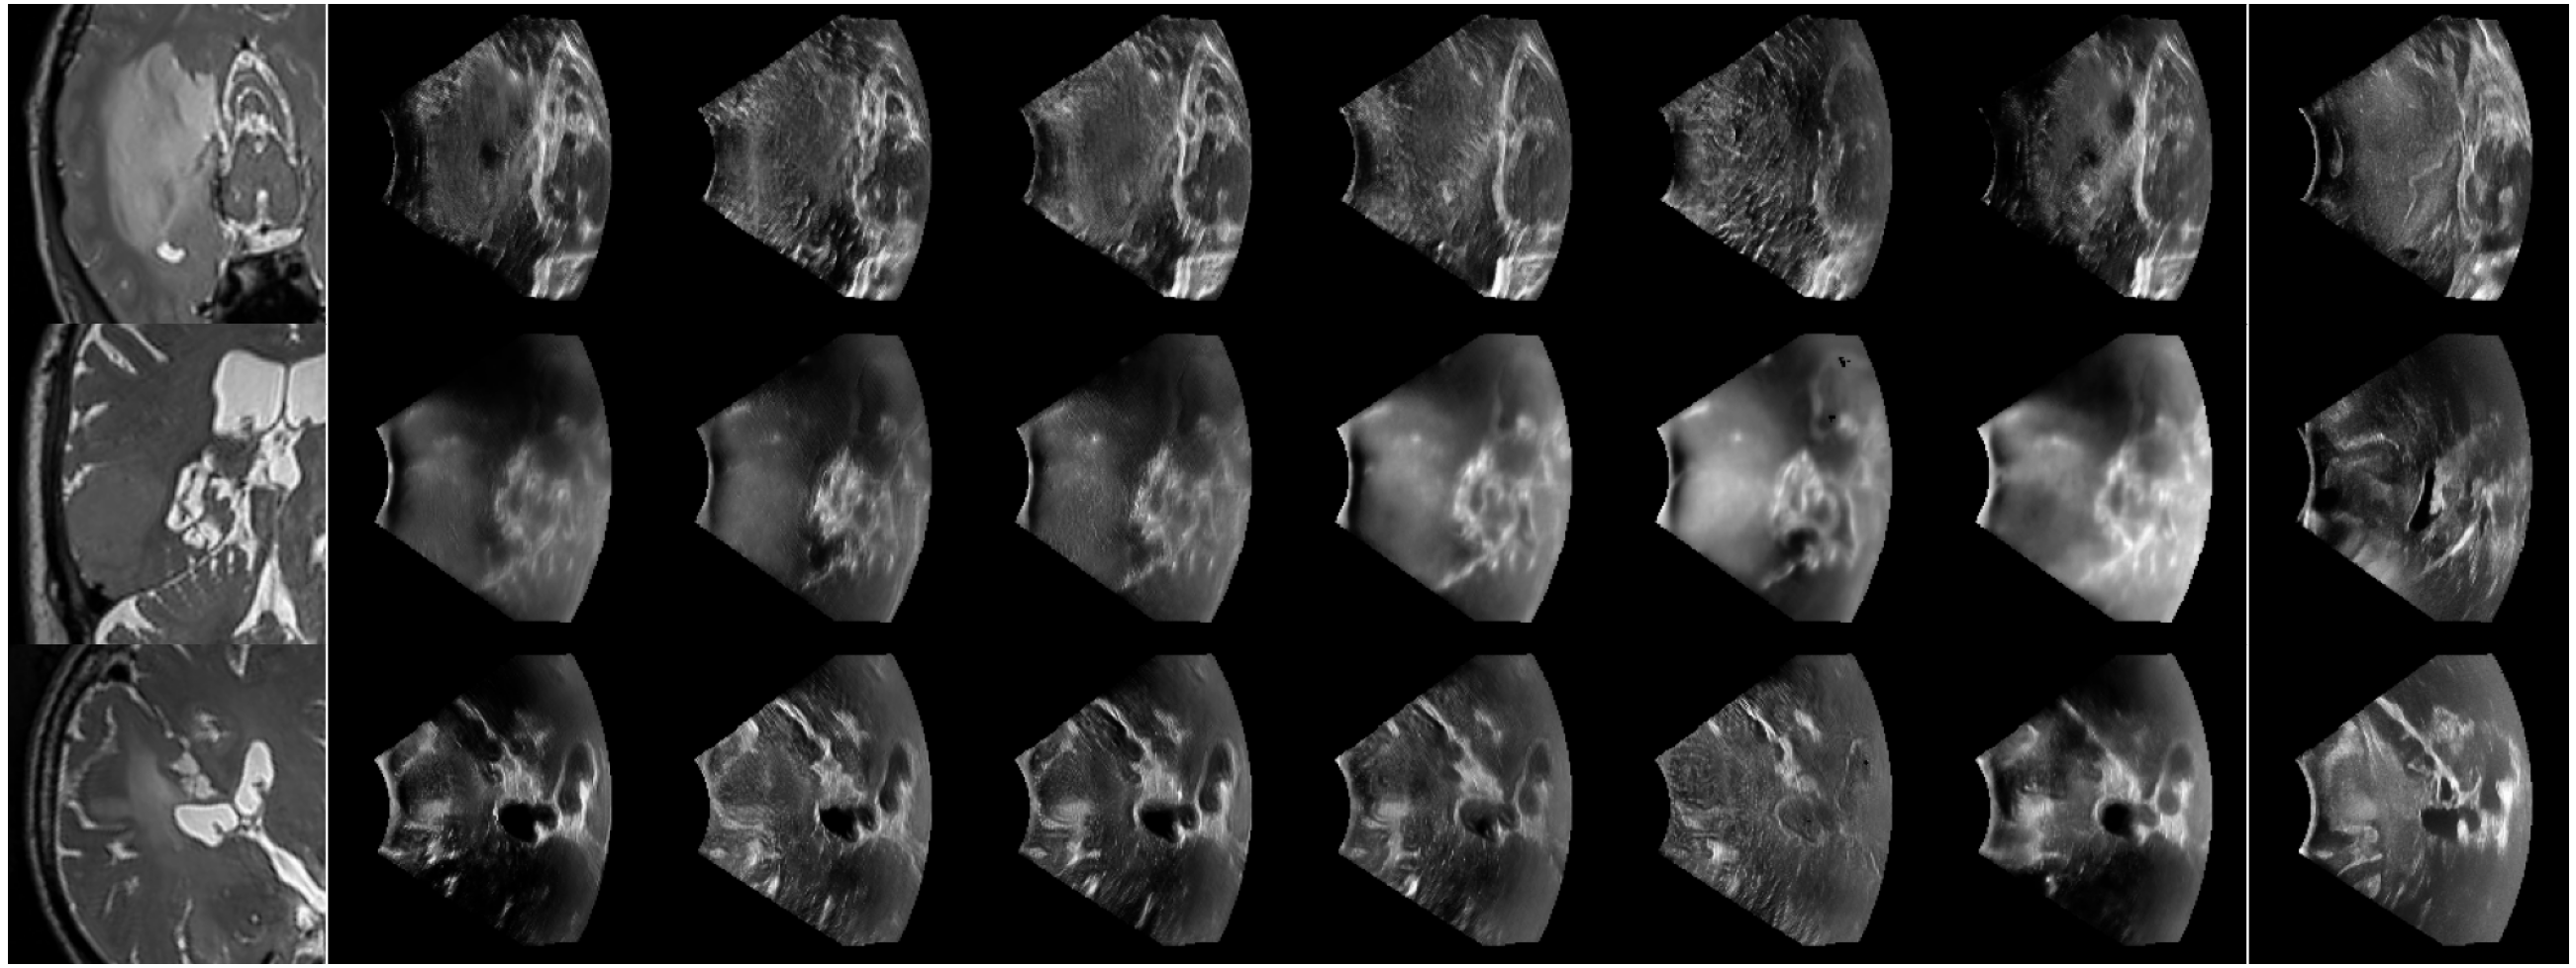

Refer to caption

Figure 2: Synthetic US image generations for three different T2 MR images (One case per row). The first column shows T2 MR; the middle columns show samples of synthetic US images generated using different combinations of T2, T1, and FLAIR with different speckles; the last column shows the ground truth US image.